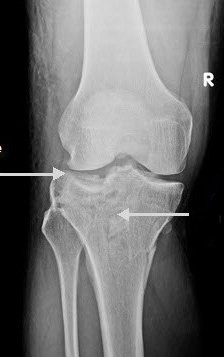

Significantly displaced tibial plateau fractures are usually treated by internal fixation.